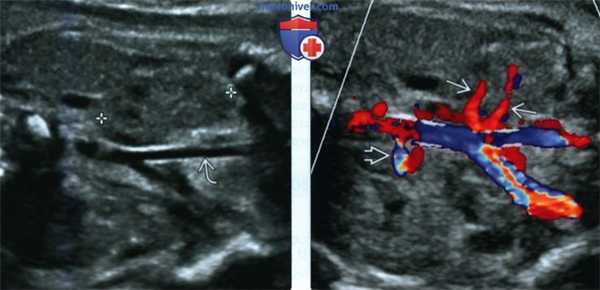

• ЦДК:

о Почечная артерия со стороны пустого почечного ложа не обнаруживается

о Источники кровоснабжения эктопической почки варьируют:

- Один или несколько сосудов, отходящих от аорты или дистальнее бифуркации

(Слева) В 29 нед. обнаружена правая эктопическая почка (калиперы) вблизи правой общей подвздошной артерии Левая почка расположена нормально (не показана).

(Справа) Для обнаружения тазовой почки при пустом почечном ложе прибегают к ЦДК. В данном случае левая почечная артерия расположена нормально, а от аорты вблизи бифуркации отходят две правые почечные артерии.